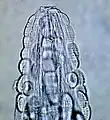

| Male Gongylonema pulchrum as seen under a light microscope.[1] | |